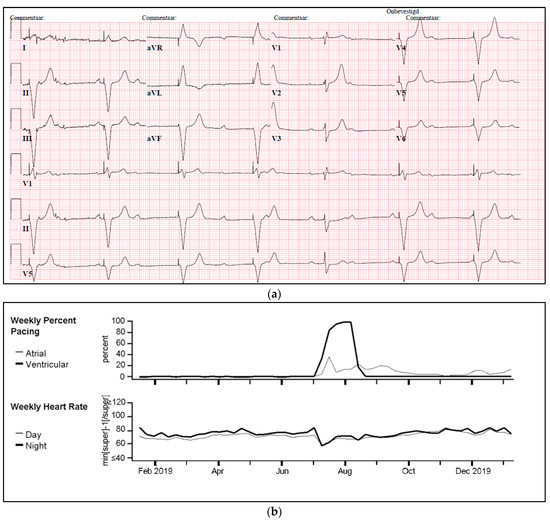

One of our cases was an adult patient with third-degree AV block caused by cardiac sarcoidosis, for which he had received a 2-lead ICD programmed in DDI-40 (dual-chamber pacing and sensing with inhibition, pacing both the atrium and ventricle, with a lower rate of 40 bpm). Over a period of seven years, remission was sustained, supported by 0% atrial or ventricular pacing and the absence of rhythm abnormalities. Subsequently, the patient presented with palpitations identified as recurrent AV block, leading to 100% ventricular pacing (Figure 5a,b). PET-CT imaging revealed a high suspicion of reactivation of cardiac sarcoidosis, with increased uptake of F-18 fluorodeoxyglucose (FDG) observed in the left ventricle, septum, and right ventricular free wall (Figure 5c). Following treatment with prednisone, remission was achieved, and the percentage pacing returned to 0%.

Figure 5.

(a) Development of atrioventricular (AV) block and ventricular pacing at lower rate. ECG Showing sinus rhythm at 80/min, third degree atrioventricular block, ventricular pacing at 30/min. (b) Device interrogation showing 100% ventricular pacing. Weekly percentage pacing and weekly heart rate, 1 year trend. A sudden rise to 100% pacing is seen. (c) F-18 FDG PET-CT whilst in remission versus recurrent episode of cardiac sarcoidosis. (A,B): F-18 FDG PET-CT transverse and coronal cross-sections showing no signs of active cardiac sarcoidosis. (C,D): F-18 FDG PET-CT transverse and coronal cross-sections showing high suspicion of reactivation of cardiac sarcoidosis with F-18 FDG uptake of the left ventricle and interventricular septum.